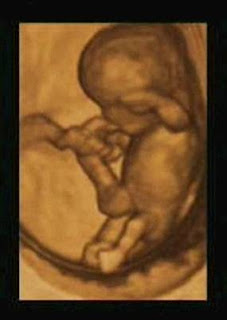

Ecografia às 10 semanas

Ser humano com 10 semanas

veja mais imagens de ecografias 3D em http://www.ecografias3d.com/20.htm